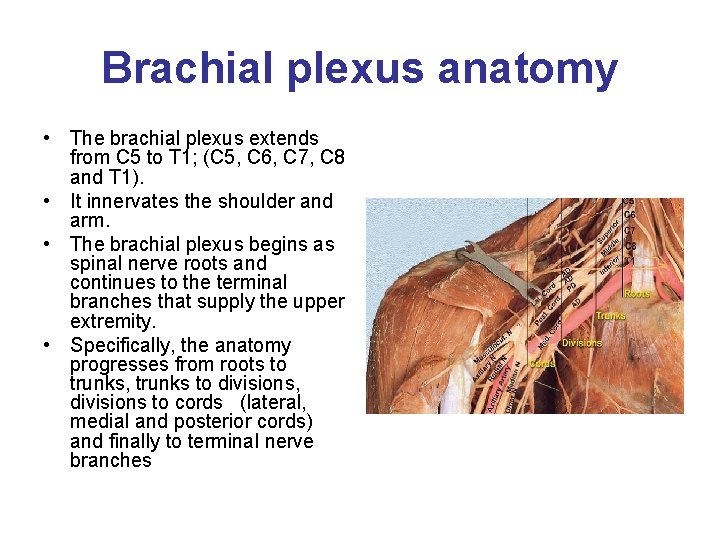

Brachial plexus anatomy • The brachial plexus extends from C 5 to T 1; (C 5, C 6, C 7, C 8 and T 1). • It innervates the shoulder and arm. • The brachial plexus begins as spinal nerve roots and continues to the terminal branches that supply the upper extremity. • Specifically, the anatomy progresses from roots to trunks, trunks to divisions, divisions to cords (lateral, medial and posterior cords) and finally to terminal nerve branches